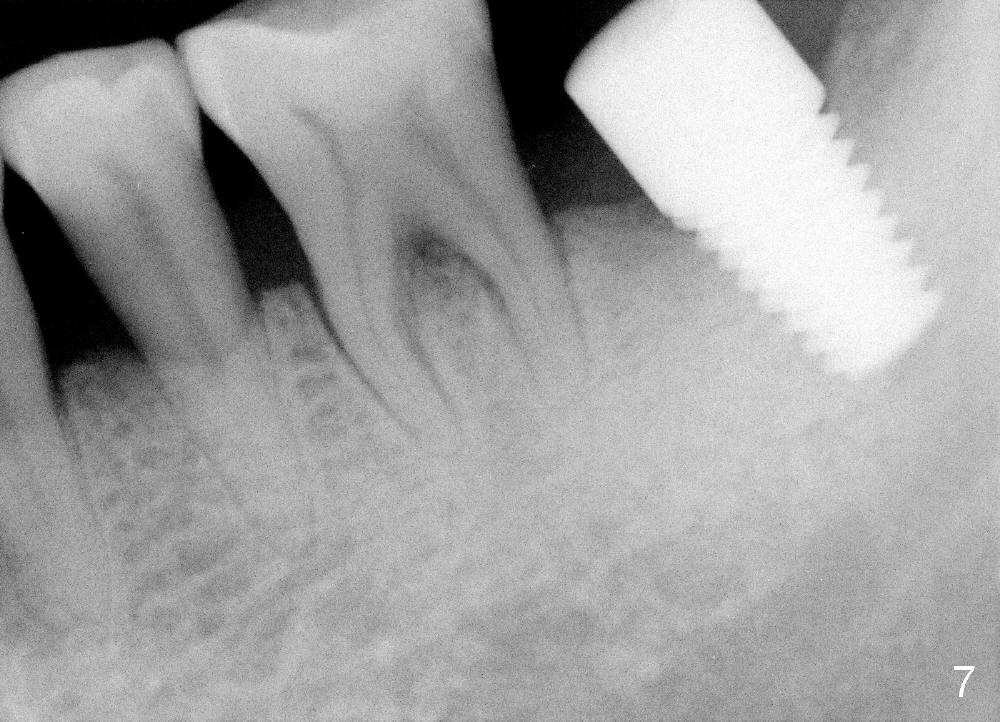

In contrast, the patient is asymptomatic after the 2nd placement.  The implant remains stable (Fig.6 (15 days postop); Fig.7 (4 months postop)).